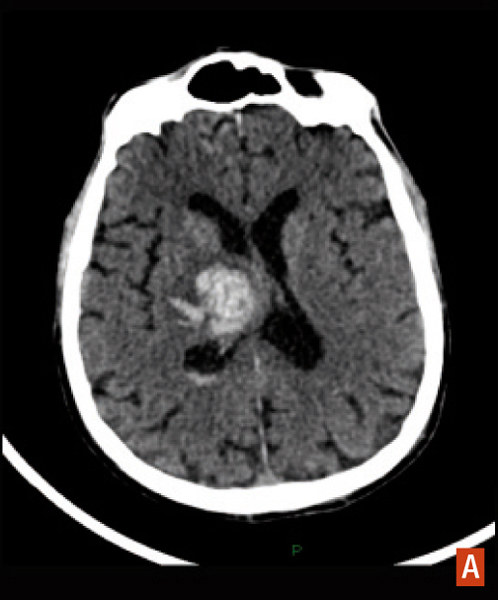

Hématome intracérébral profond

TDM cérébrale sans injection, hyperdensité spontanée.